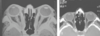

Estudios de imagen para valorar orbita

RM , TC y USG

Prueba dx en oftalmopatía tiroidea

TC (músculos engrosados)

Estudio de imagen para seudotumor

Tc (mejor) o USG modo A y B